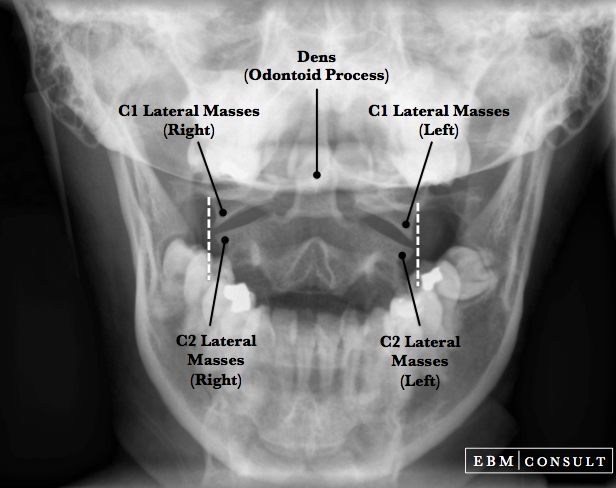

- The rule of Spence is a radiographic method that attempts to determine the integrity of the transverse ligament when doing an

open mouth (odontoid view) radiograph.

- If the combined measurement of the right and left lateral masses of C1 hang over the lateral masses of C2 by more than 6.9 mm then there should be concern for a possible transverse ligament injury and the patient should get an MRI or flexion or extension imaging.